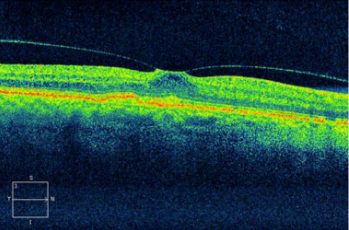

【求助】玻璃体黄斑牵拉综合征

玻璃体黄斑牵拉一例自行恢复实属万幸